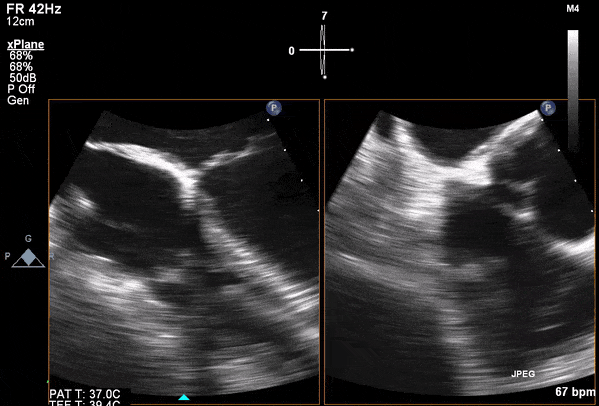

Transesophageal Images